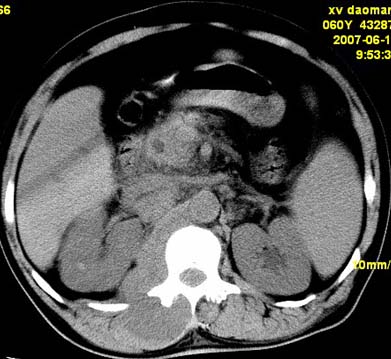

以下是引用还珠格格在2007-6-26 15:05:00的发言:[br]右侧腰大肌、同侧竖脊肌明显肿胀,呈不均匀密度减低影,右肾受压右上前移,脂肪间隙部分消失,另左侧肾盂内可见高密度影,是结石还是造影剂? 不知道病人用造影剂没有?考虑 右侧腰大肌及右侧竖脊肌寒性脓肿形成。[br][br][本贴已被 还珠格格 于 2007-6-26 15:21:35 修改过]

以下是引用小初学者在2007-6-26 15:42:00的发言:[br]1\\右侧腰大肌、同侧竖脊肌脓肿[br]2\\左侧肾盂结石

以下是引用刘明在2007-6-26 16:00:00的发言:[br][br]右侧竖直肌及腰大肌肿胀,脂肪间隙难辨,腹膜后血管旁见多个肿大淋巴结影,椎体附件右侧有压迫吸收、未见硬化迹象,考虑椎旁冷脓肿可能[br]左侧肾盂内可见高密度影,周围有毛刺,本图象是平扫,不是增强,应该是结石[br]